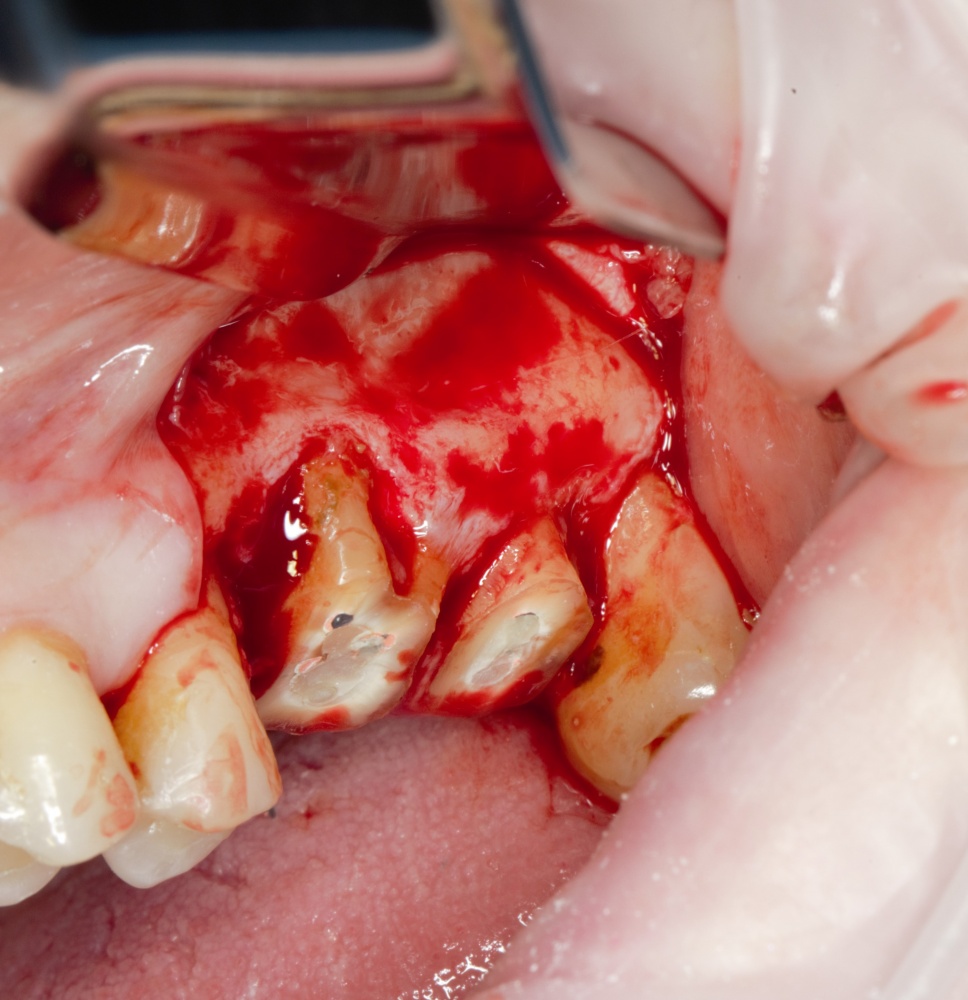

Простой синуслифтинг. Часть I.